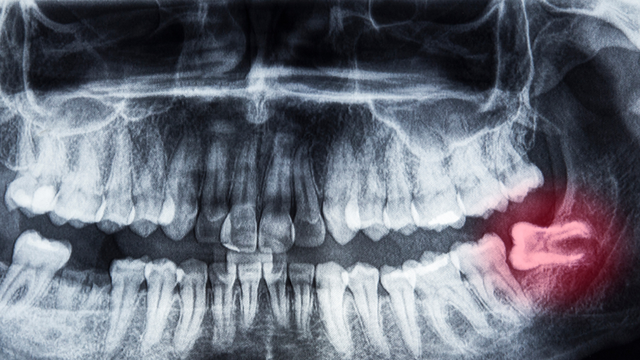

:format(webp)/tai_sao_moc_rang_khon_bi_dau_ham_4_39ca512aab.png)

Răng khôn, hay còn gọi là răng số 8, thường xuất hiện ở độ tuổi từ 17 đến 25. Mọc răng khôn có thể gây ra nhiều vấn đề khó chịu, đặc biệt là đau hàm. Tình trạng này không chỉ ảnh hưởng đến sức khỏe răng miệng mà còn gây ra những phiền toái trong sinh hoạt hàng ngày. Vậy tại sao mọc răng khôn bị đau hàm và làm thế nào để giảm bớt cảm giác này? Hãy cùng tìm hiểu trong bài viết dưới đây để có cái nhìn tổng quan và biết thêm những biện pháp chăm sóc răng miệng hiệu quả.